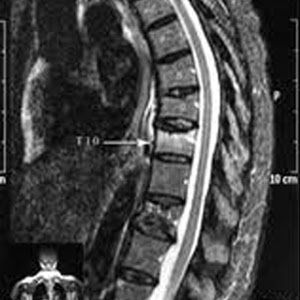

Risonanza magnetica (MRI) fornisce informazioni sull’infiltrazione del mieloma nel midollo osseo. Il tumore al midollo osseo può essere di differenti tipi: leucemia acuta o cronica, malattia di Kahler o mieloma. Le prime provocano un’anemia che si manifesta con una eccessiva stanchezza e un intenso pallore, fratture spontanee delle ossa colpite e. Sono presenti cinque tipi di immunoglobuline: A, G, M, D ed E. Articolo realizzato dalla redazione Informazioni sui Consulenti Scientifici.

Il mieloma , detto anche mieloma multiplo perché colpisce più sedi all’interno dell’organismo, è un tumore che nasce nel midollo osseo , dove un linfocita B subisce un’alterazione genetica e trasmette caratteristiche tumorali a tutte le cellule che ne discenderanno, dei globuli bianchi denominati plasmacellule deputati alla produzione degli anticorpi. Il midollo osseo è un tessuto specifico all'interno delle ossa. Cancro del midollo osseo : tipi e sintomi.